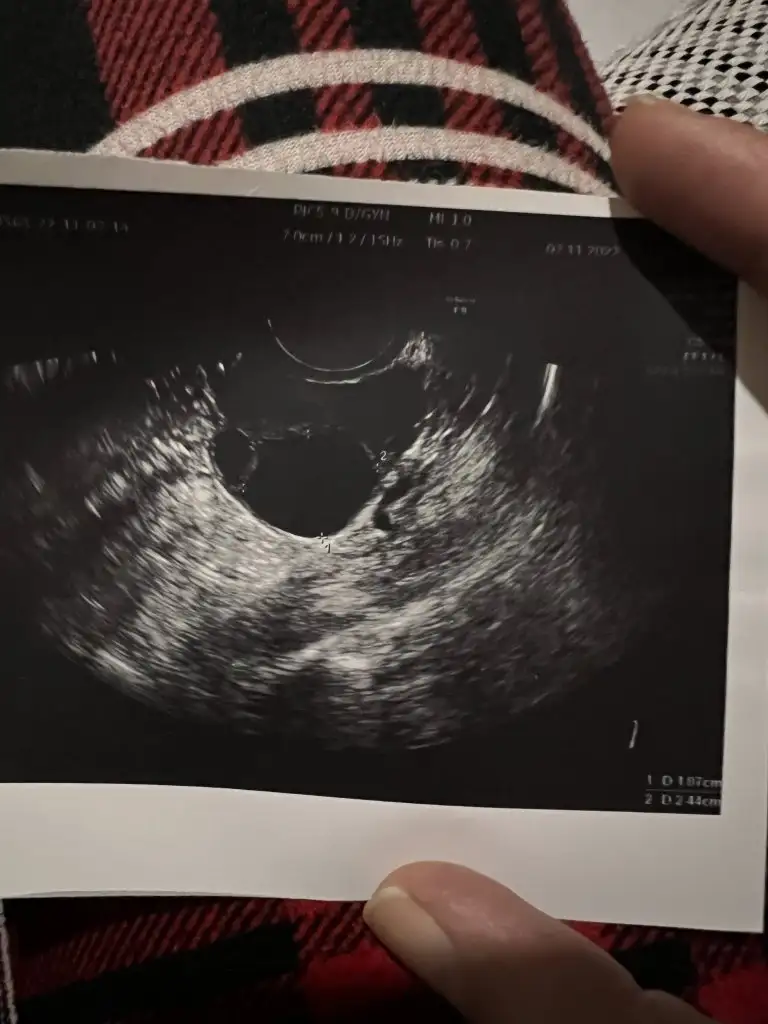

Çok ta anlaşılmıyor ya da düz bir açıdan çekilmiş bak benim eskilerden birini atıyorum şimdi ama resimden ziyada sağ alt köşesinde kaç ml olduğu yazıyor 1,87 2,44 cm yazıyor mesela senin kağıdın bir tarafında yok mu bu bilgi

Sizin en altta küçük bir tane yazıyor ama çok küçük diye mi acaba doktor yok dedi, o da olabilir. Evet progesteron testiyle anlaşılıyor o ay yumurtlama olup olmadığı, onu da ortalama döngü 28 gün üzerinden hesapla 21. gün istiyorlar, içinde kalcağına bence baktır canım aklında kuşku olmasın en azından

Ultrason fotoğrafımda işaretlenmiş iki nokta gördüm onların folikül olduğunu tahmin ediyorum ama dediğim gibi çok kötü bir doktora denk geldim kafam karıştı. Önerdiğiniz hormon testini vereceğim çok teşekkür ederim 💞🌺

O karartılar zaten kist değilse ki olsa illa söylerdi , aynen folikül oluyor ama çok küçük diye herhalde yok deyip geçiştirdi mi ne yaptıysa. Kadın doğum doktorunda doktor işi şans işi gerçekten inanıyorum ben artık.geçen gün öyle birine denk geldim ne sorsam tüp bebekçiler söylesin dedi adam sonra çıktım şikayet ettim adamı o kadar sinir oldum , sen ne işe yarıyorsun o zaman diyecektim ama eşim yanımda laf olur kavga olur bilmem ne derken bide sağlıkta şiddet haberlerinden biri de biz olmayalım diye tuttum kendimi velhasıl. Ama şikayetimi de ettim , ulaşır ulaşmaz bilmem ama sinirimi kustum o da yetti bana😂